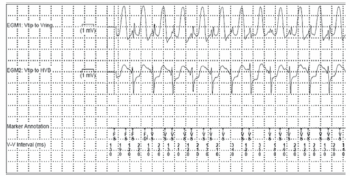

Um paciente de 32 anos, com diagnóstico de cardiomiopatia hipertrófica, portador de CDI unicameral para profilaxia secundária de morte súbita, apresentou terapia de choque pelo dispositivo durante exercício físico aeróbico.

A interrogação por telemetria do dispositivo revelou eventos de alta frequência ventricular com o seguinte padrão no eletrograma intracavitário

Assinale a opção que apresenta a provável causa do ritmo apresentado e a interpretação sobre a terapia gerada.